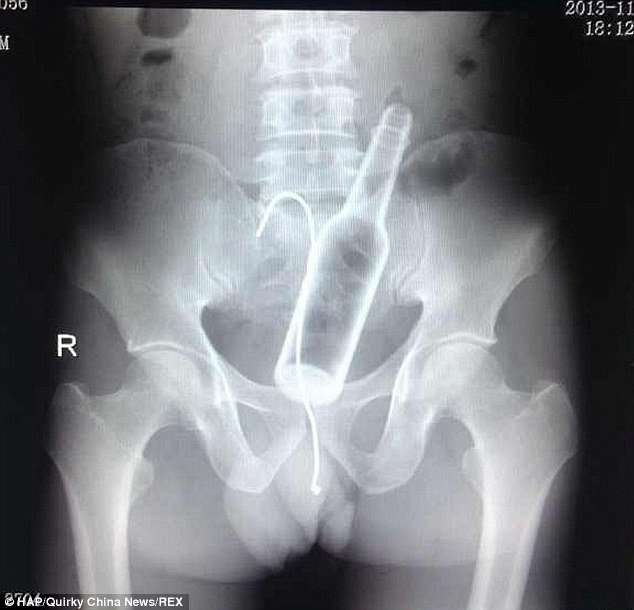

Բժիշկները, ռենտգեն հետազոտություն են արել և ցնցվել են՝ լուսանկարներում տղամարդու աղիքներում շիշ և մետաղալար հայտնաբերելով:

Այդ ժամանակ տղամարդը խոստովանել է, որ շիշը ինքնուրույն է տեղադրել հետանցքի մեջ, սակայն հետագայում չի կարողացել այն դուրս բերել: Սարսափահար եղած նա հիշել է ձկնորսական հմտությունների մասին և փորձել մետաղալարով դուրս հանել շիշը:

Նրա գործողությունների արդյունքում աղքիներում շշի հետ միասին հայտնվել է նաև մետաղալարը: Վիրաբույժների ջանքերի շնորհիվ առարկաները տղամարդու մարմնից դուրս են բերվել: Սակայն դրանով խնդիրները չեն ավարտվել, քանի որ շիշն ու մետաղալարը վնասել են նրա աղիքները, և այժմ նա պետք է բուժման երկարատև կուրս անցնի: